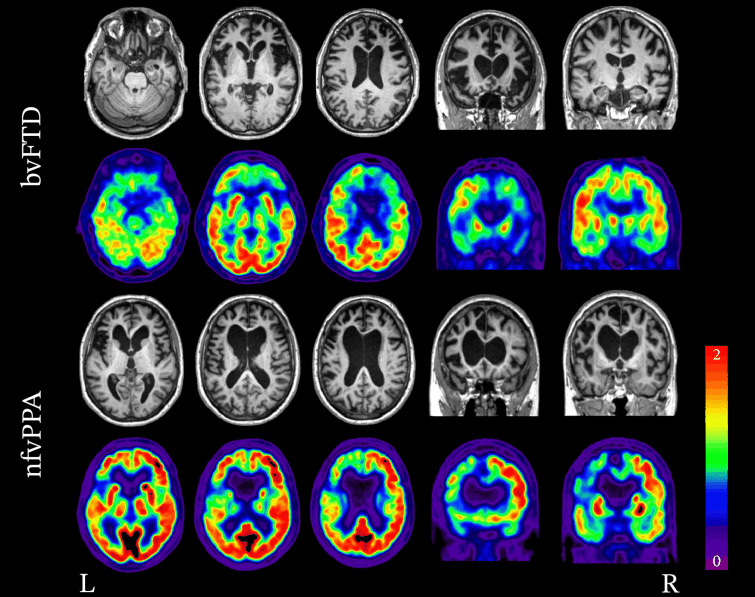

A RNM é a principal modalidade de imagem para o diagnóstico de DFT e deve ser solicitada se houver suspeita de um diagnóstico de demência frontotemporal.[104][106][Figure caption and citation for the preceding image starts]: Padrões de neuroimagem associados à variante comportamental da DFT (vcDFT) e à variante não fluente da afasia progressiva primária (vnfAPP). RNM estrutural e FDG-PET demonstrando a variabilidade nos padrões de atrofia e hipometabolismo na DFT. No caso da vcDFT, observa-se atrofia bilateral significativa e hipometabolismo no lobo frontal. No caso da vnfAPP, a atrofia e o hipometabolismo são lateralizados e afetam muito mais o lobo frontal esquerdo do que o direito.Peet BT et al. Neurotherapeutics 2021 Abr; 18 (2): 728-52; usado com permissão [Citation ends].

A FDG-PET/CT pode ajudar a diferenciar a demência frontotemporal da doença de Alzheimer e da demência com corpos de Lewy.[103][104][105] Ela é mais útil quando combinada com a RNM.[104][Figure caption and citation for the preceding image starts]: Padrões de neuroimagem associados à variante comportamental da DFT (vcDFT) e à variante não fluente da afasia progressiva primária (vnfAPP). RNM estrutural e FDG-PET demonstrando a variabilidade nos padrões de atrofia e hipometabolismo na DFT. No caso da vcDFT, observa-se atrofia bilateral significativa e hipometabolismo no lobo frontal. No caso da vnfAPP, a atrofia e o hipometabolismo são lateralizados e afetam muito mais o lobo frontal esquerdo do que o direito.Peet BT et al. Neurotherapeutics 2021 Abr; 18 (2): 728-52; usado com permissão [Citation ends].